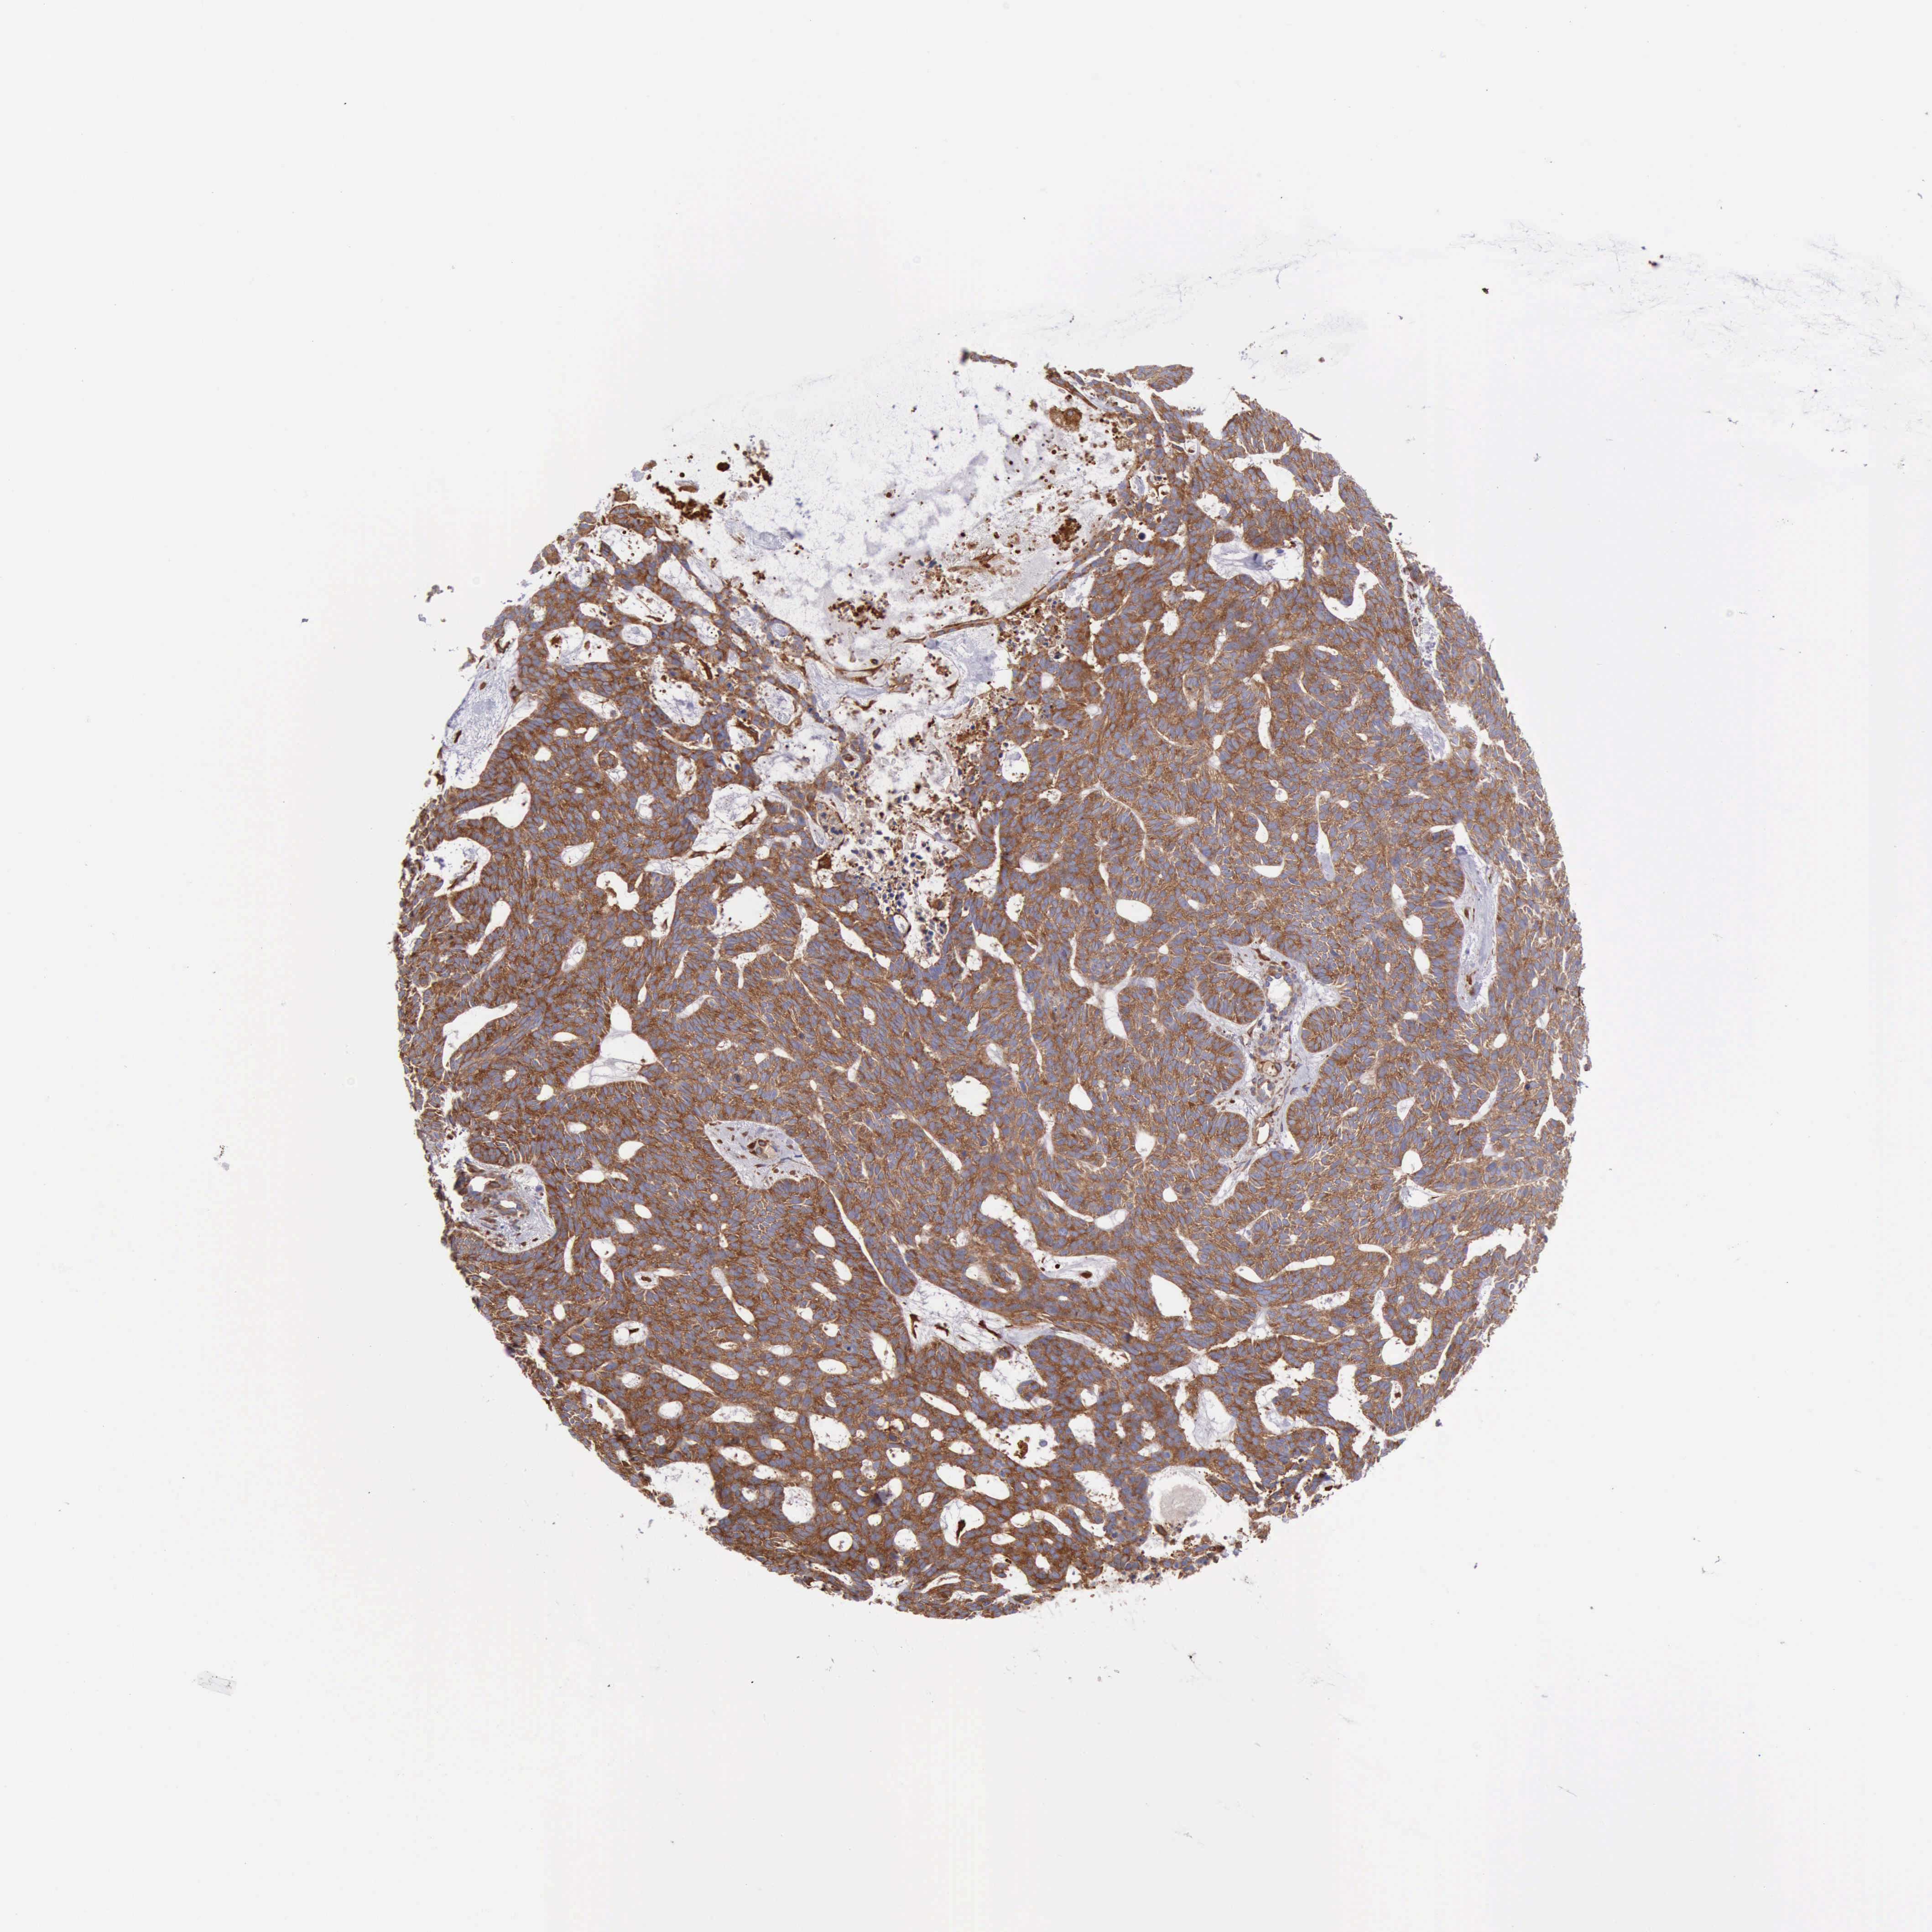

SKIN CANCER - Protein expressioni

A mouse-over function shows sample information and annotation data. Click on an image to view it in a full screen mode. Samples can be filtered based on level of antibody staining by selecting one or several of the following categories: high, medium, low and not detected. The assay and annotation is described here.

Each image is clickable and will lead to virtual microscopy that enables deeper exploration of all samples and also displays staining intensity scores, fraction scores and subcellular localization as well as patient and tissue information for each sample.

Antibody HPA001115

Antibody HPA002925

Antibody CAB000356

Staining

High

Medium

Low

Not detected

Intensity

Strong

Moderate

Weak

Negative

Quantity

>75%

75%-25%

<25%

None

Location

Nuclear

Cytoplasmic/membranous

Cytoplasmic/membranous,nuclear

Squamous cell carcinoma, NOS

Basal cell carcinoma